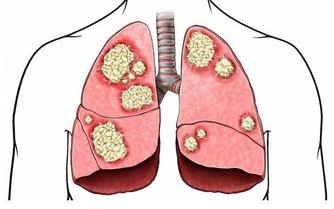

3、指甲呈扁圓型

有時候指甲的形狀會出現2種改變方式,一種是指甲呈現扁圓狀改變,另一種則呈現半圓形改變。如果你的指甲扁圓形改變,說明你的腸味淤積的毒素過多,可能還伴有慢性腸炎、消化不良等腸胃疾病。一般此類病人還會有營養代謝障礙,這樣一來就會影響其他臟器的正常運行,特別是對肺部的影響較大。